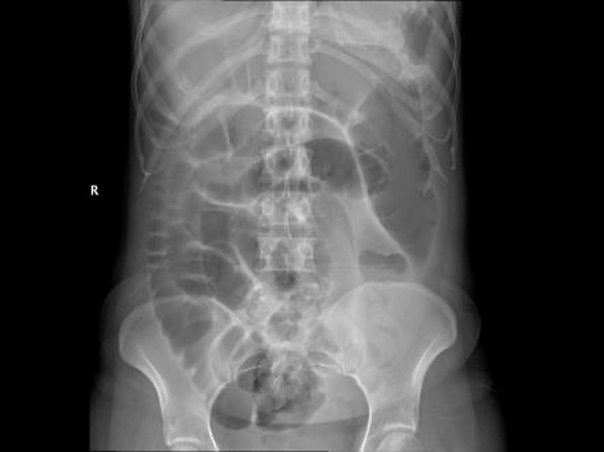

Small bowel obstruction

Large bowel obstruction

General approach for AXR interpretation

SBO vs LBO